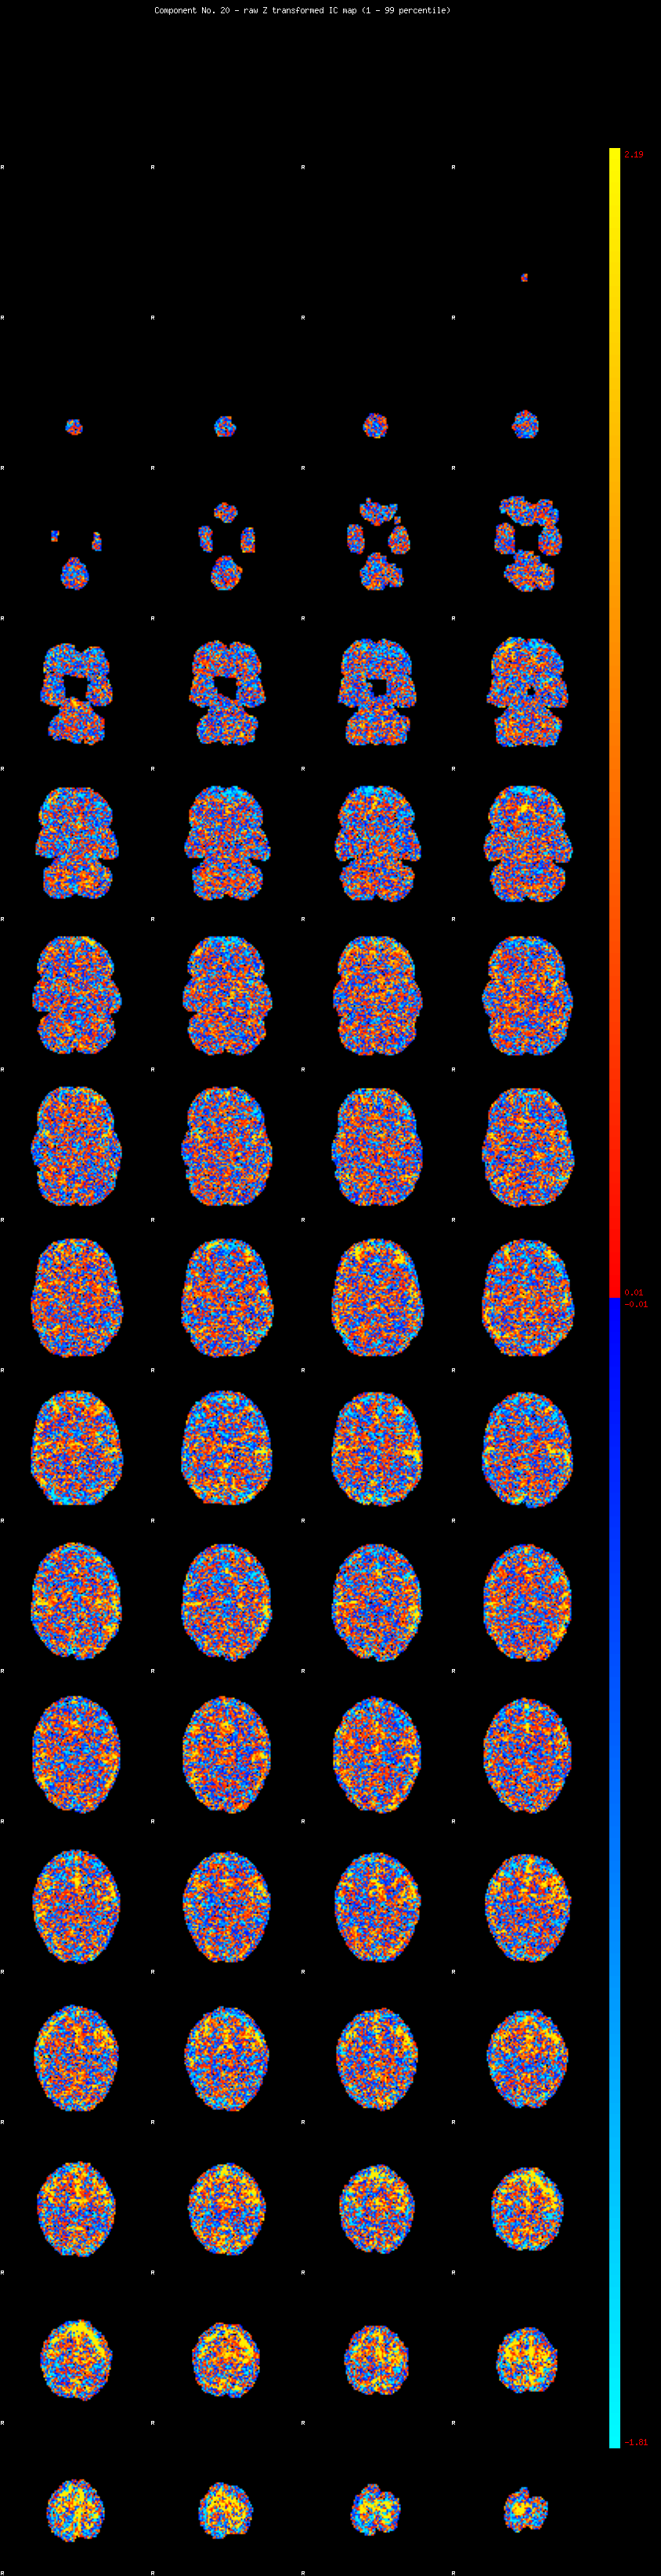

IC_20 Mixture Model fit

Means : -0.000000 3.331853 -2.816083

Vars : 1.000000 5.171210 0.606418

Prop. : 0.949612 0.041476 0.008911